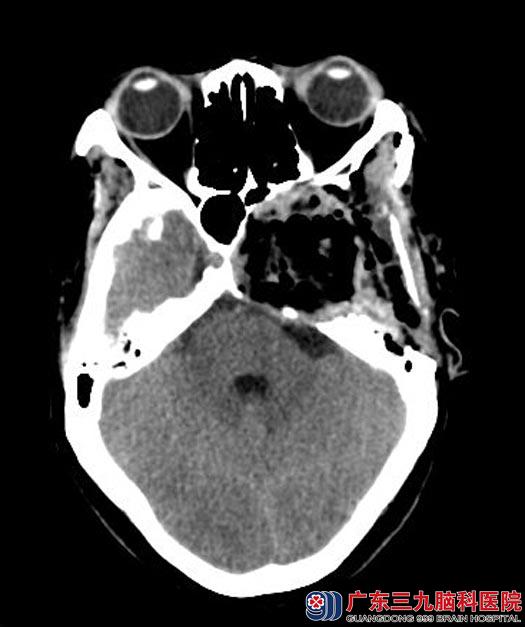

讨论后,决定由鲁明主任主刀,在全麻下行左侧前、中、后颅窝巨大肿瘤切除术,术中显微镜下见灰白色肿瘤组织,肿瘤位于硬膜外,边界清,血供一般,予显微镜下小心分离,分块切除,肿瘤与海绵窦粘连紧密,小心剥离后将肿瘤全切,视神经、动眼神经、滑车神经、外展神经、三叉神经均保护完好。术后丽姐感觉双眼视力明显好转。病理结果:神经鞘瘤。

手术后